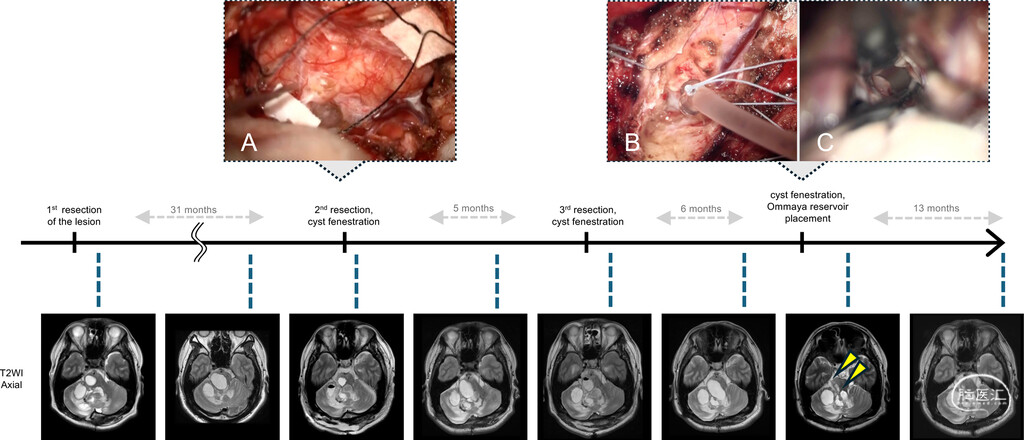

4.Ommaya囊植入:约6个月后,复查可见囊性病灶进一步增大并压迫脑干。为实现持久的囊肿减压,首先在导航引导下置入8Fr Nelaton导管(Terumo),对多房囊肿进行开窗。随后将8Fr导管更换为10Fr导管,逐步扩张通道,扩大开窗口并建立囊肿腔与桥小脑角池之间的沟通,使脑脊液能够持续流出。再沿同一通道置入Ommaya囊(Integra Life Sciences),以保留囊肿系统的穿刺通路,为后续可能的减压操作提供安全保障。术后CT证实Ommaya囊导管末端位于脑池内。

图2:临床病程、手术干预及系列T2WI表现图示为各手术阶段的代表性术前与术后影像。A:第二次切除术中所见:小脑叶片轻度肿胀、色泽苍白,与周围正常组织边界不清,表面可见囊性改变。B、C:Ommaya囊置入术中所见:B:在导航引导下置入Nelaton导管建立通道。C:沿导管通道对多房囊肿分步开窗,实现脑脊液持续流出并与脑池相通;于通道近端置入Ommaya囊,以备囊肿再次扩大时使用。

截至最近一次随访(Ommaya囊置入术后1年),患者已可独立行走。连续MRI复查显示囊肿持续缩小并保持稳定,未再增大,且无需经Ommaya囊穿刺抽吸(图2)。

本例强调了针对囊性变异型LDD制定个体化手术策略的重要性,核心在于重建脑脊液通路,而非追求病灶的根治性切除。本研究仅为单病例报道,且患者拒绝多基因检测,因此缺乏遗传学分析。Ommaya囊置入对部分患者而言,可能是预防囊肿反复增大的安全有效方法。未来需积累更多相似病例,以阐明其病理生理机制并确立最佳治疗方案。